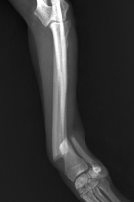

橈尺骨の骨折

上腕骨の骨折